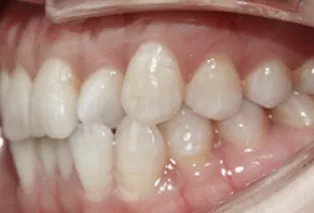

Intraoral photos